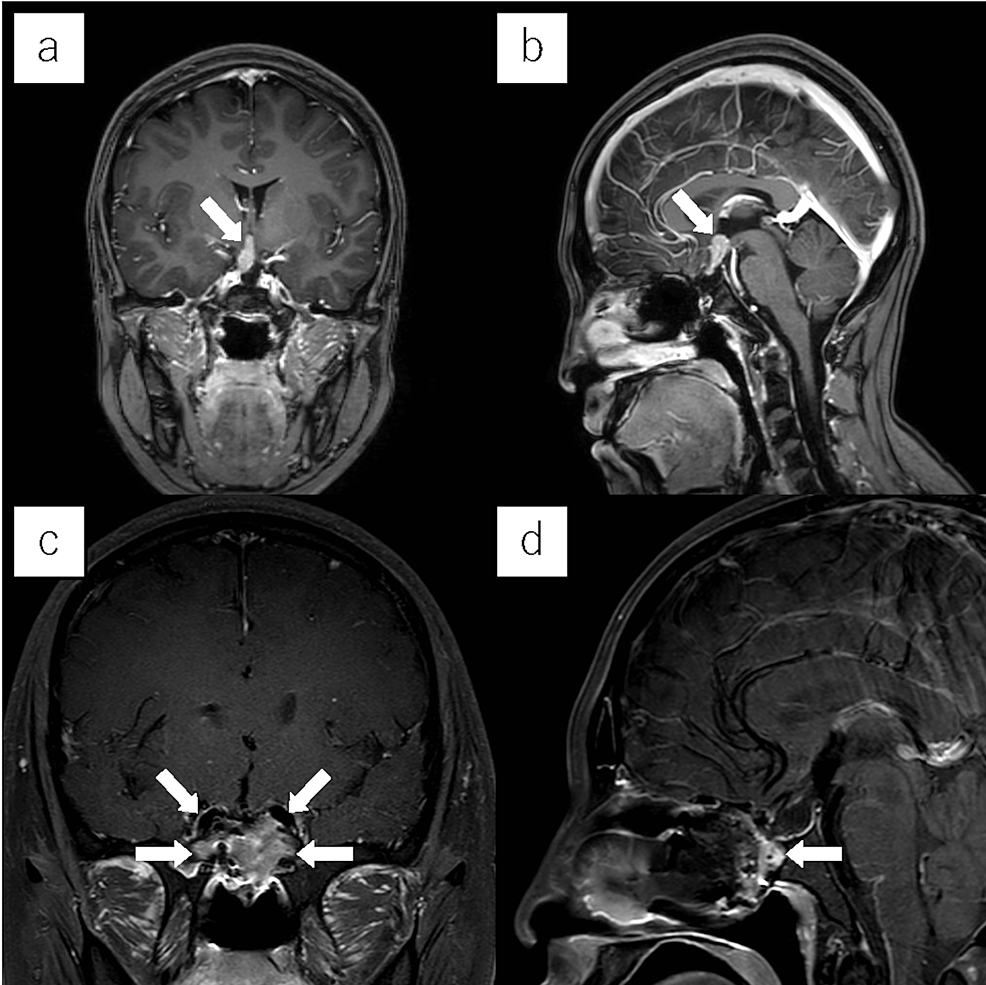

From www.mdpi.com

JCM Free FullText ColorectalVaginal Fistulas Imaging and Novel What Is Take Down Surgery During this time, you’ll gradually regain your energy and strength. Anastomotic leak—when the bowel joining doesn’t heal properly and it leaks feces into the abdomen; An ileostomy closure surgery is done to reverse your ileostomy so you can have bowel movements like you did before your. There are also risks of colostomy reversal surgery itself including: Colostomies that are used. What Is Take Down Surgery.